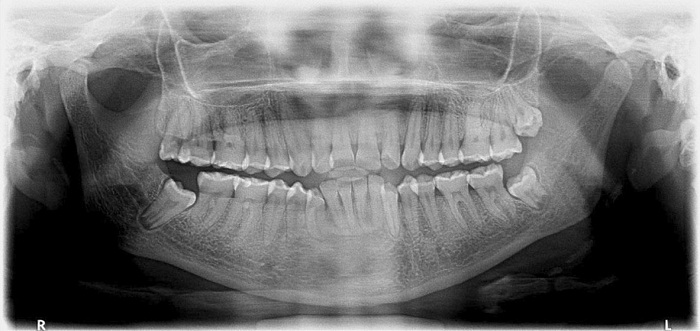

Entre los antecedentes odontológicos se reportaron cuatro gingivectomías entre 2004 y 2008. En el examen clínico extraoral la paciente evidenciaba quintos asimétricos, tercio medio disminuido, perfil convexo e incompetencia labial. En el examen clínico intraoral se registró sobremordida horizontal y vertical, malposiciones y apiñamiento dental. Periodontalmente, se observó aumento en el volumen del tejido gingival en las superficies vestibulares, palatinas y linguales de incisivos, caninos y premolares. El sondaje reveló bolsas gingivales con un rango de profundidad de 4 a 6 mm, acompañado de eritema, sangrado y cálculos subgingivales. La paciente tenía una higiene oral deficiente con un porcentaje de placa del 84,3 %, según el Índice de O’Leary (figura 1). Se notificó que su frecuencia de cepillado era de una vez al día y que no utilizaba elementos complementarios de higiene oral. La figura 2 corresponde a la radiografía panorámica en la que se observan crestas óseas de altura normal.